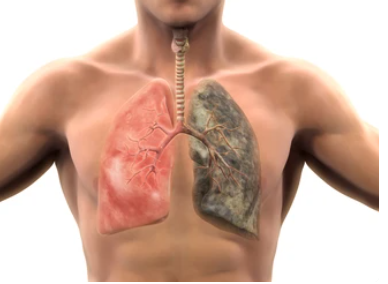

폐암 원인

폐암의 가장 주요한 원인으로는 흡연입니다. 흡연은 암 발생의 주요 위험 요인 중 하나로 알려져 있으며, 약 85%의 폐암 환자가 흡연과 밀접한 관련이 있습니다. 흡연은 담배 연기에 함유된 많은 유해한 화학 물질을 호흡기계로 흡입하여 폐 조직을 손상시킵니다. 하지만 비흡연자라고 해서 안심할 수는 없습니다. 흡연 외에도, 여러 가지 요인들이 폐암 발생 위험을 높일 수 있습니다. 여성 폐암 환자의 80% 이상은 흡연을 한 적이 없다고 합니다.

이러한 비흡연 여상의 폐암은 간접흡연, 미세먼지, 환경오염, 유해물질노출, 음식 조리 시 발생하는 오염물질등이 폐암 원인으로 볼 수 있습니다. 특히환기시설이열악하고,고온의기름을많이사용하는조리시설환경에서폐암의발생위험률이매우높을수있습니다.